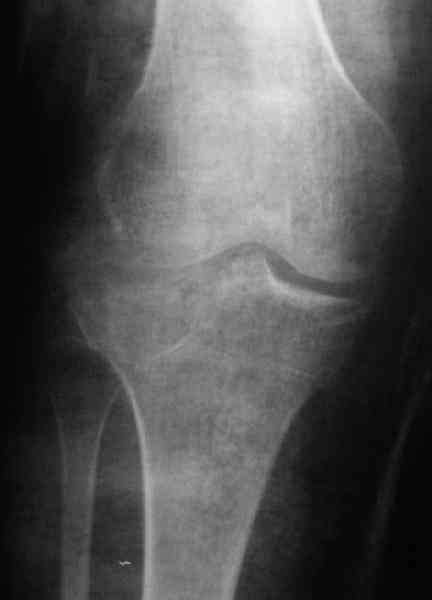

[Ortho] Застарелый перелом 41С3

Уважаемый Абдурашид. Если нет противопоказаний , то из оперативных

способов, я бы рекомендовал следующие: Полное замещение наружного

мыщелка аллотрансплантатом либо открытая репозиция с элевацией и

замещение дефекта ауто или аллокостью. В Ваших условиях , я бы

рекомендовал второй способ. Во-время элевации необходимо разъединить

фрагменты со стороны сустава ( надсечь скальпелем по линиям перелома,

а затем тонким остеотомом их разъединить. При помощи долота произвести

неполную остеотомию ( захватите не менее 1,5 - 2 см губчатой кости и

поднять фрагменты, визуально отрепонировать и фиксировать 2-3 спицами.

Дефект заместить костным ауто или аллотрансплантатом. Окончательная

стабилизация пластиной ( лучше с угловой стабильностью, либо АВФ -

позволит спокойно устранить угловую деформацию.